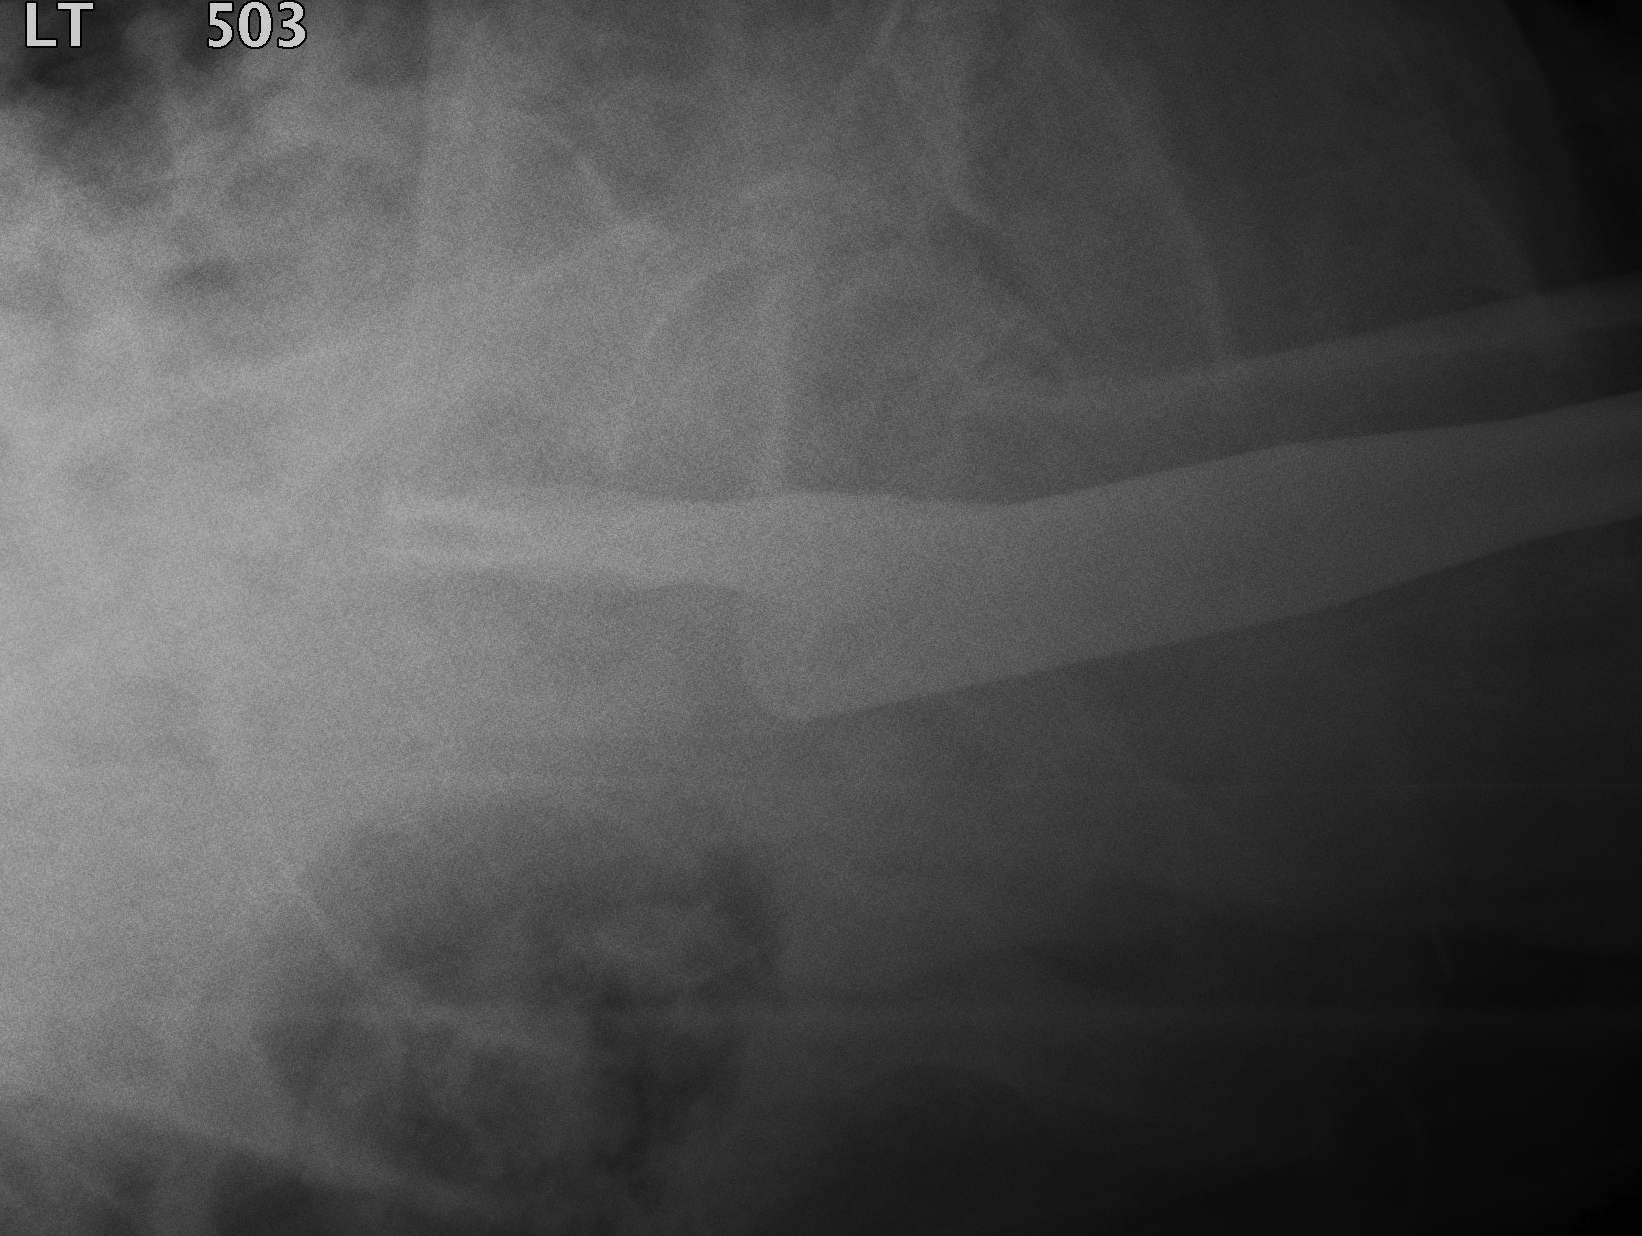

Fracture which extends between the trochanters of the proximal femur

Extra capsular / well vascularized

Evans Classification

Two main types

- Type 1 Intertrochanteric

- Type 2 Reverse Oblique

Type 1 Intertrochanteric

2 part undisplaced

2 part displaced

3 part without posterolateral support (GT fracture)

3 part without posteromedial support (LT fracture)

4 part without posterolateral or posteromedial support

Type II Reverse Oblique Type

Inherently unstable - tendency of femoral shaft fragment to shift medially

Reverse oblique fractures